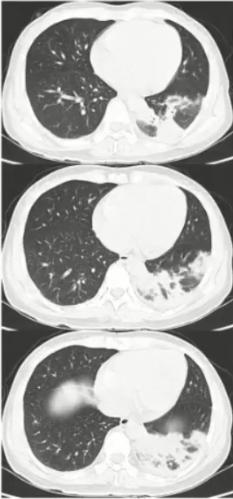

病例6

女性,14岁,学生。发热、咳嗽10天入院。

院外治疗经过

• 第1-3天:阿奇霉素治疗3天(口服2天+静脉1天)无效,胸片示左上肺及右下肺斑片影

• 第4-5天:头孢曲松+阿奇霉素+小剂量激素2天无效,肺CT示左上肺大片实变及右下肺斑片影

• 第6-7天:头孢曲松+阿奇霉素+甲泼尼龙40mg bid 2天仍无好转,出现呼吸困难,CT示肺内病变进一步增多,血常规7.8×109/L、N 82.9%,CRP 43.16 mg/L,动脉血气分析PH7.42 PaO246mg Hg。

• 第8-9天:美罗培南+利奈唑胺+甲泼尼龙 80mg/d,体温无下降,呼吸困难加重,吸氧8-10L/min,指脉氧80%左右,G试验154.7,加用伏立康唑,行气管插管机械通气,病情仍无改善转来我院。

图6 患者在院外胸部影像学变化。左上肺小块实变,逐渐累积至右下肺,而且左上肺实变扩大和膨胀不全。

图8 患者入院当日胸部CT。左上肺大面积实变,右上肺斑片影,出现胸腔积液